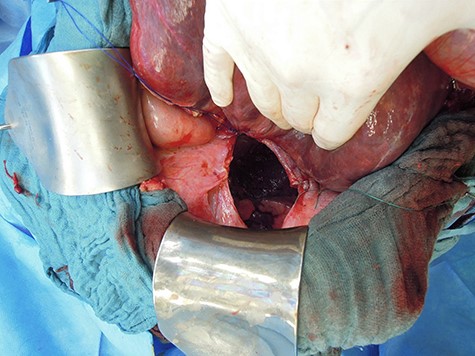

Revision laparotomy was performed, which showed a large diaphragmatic hernia on the right with intrathoracal right liver lobe, small bowel and colon (Fig. 5). The left-sided suture and mesh augmentation remained intact (Fig. 6). Due to the extended defect, only partial tension-free closure was possible, a Parietene composite® mesh was used (Figs 7 and 8) for bridging. Because of high intraabdominal pressure, primary abdominal wall closure was not possible; a gradual closure with an initially bridging vicryl mesh and vacuum therapy was performed (Fig. 9).